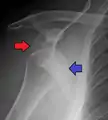

A Hill–Sachs lesion is an impaction of the head of the humerus left by the glenoid rim during dislocation.[5] Hill-Sachs deformities occur in 35–40% of anterior dislocations. They can be seen on a front-facing X-ray when the arm is in internal rotation.[8] Bankart lesions are disruptions of the glenoid labrum with or without an avulsion of bone fragment.